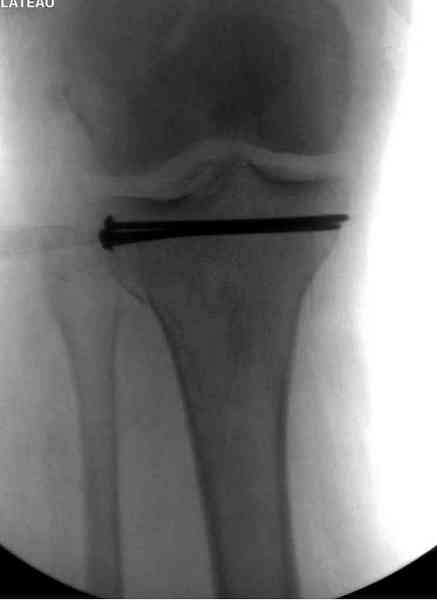

Снимки до и после закрытой репозиции

Как всегда прекрасная презентация. Совершенно согласен с необходимостью сохранять мениск и вообще согласен со всем, кроме одного. Фиксация должна проводиться после правильно выполненной репозиции. Главная цель репозиции - это восстановить высоту наружного мыщелка. В норме наружный мыщелок выше внутреннего на 4-5 мм на снимке в переднее заднем направлении АР.

Необходимость репозиции возникает при снижении высоты от 3 до 5 мм по разным источникам. По моему опыту 4 мм. Если не восстановить высоту мыщелка возникает вальгизация коленного сустава с относительным расслаблением передней крестообразной связки. При этом развивается нестабильность коленного сустава из-за недостаточности ПКС.

На представленном после операционном снимке нет репозиции, на что указывает низкое положение тибиального плато и перекрытие кортикальных пластинок в метафизарной части - указано стрелкой. Обычно чрескожную фиксацию я применяю